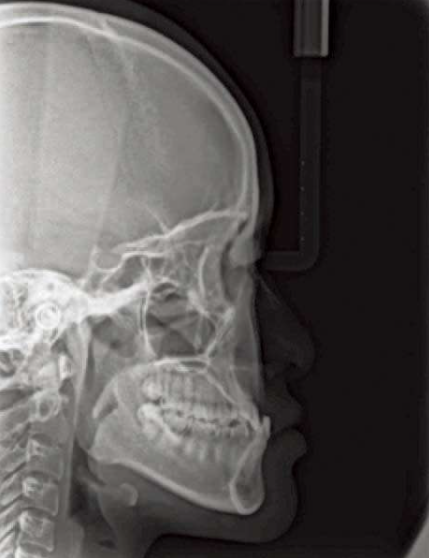

头影测量中有一个方法简单有效:

从N点(鼻根点)做眶耳平面的垂线,即Mcnamara线,上颌骨A点(上齿槽座点)距离该垂线的正常距离:0mm(儿童),1~2mm(成人);

下颌骨Pog点(颏前点)距离该垂线的正常距离:−6mm(儿童),−2mm(成人)。

图11 鉴别上下颌位置

①Pog点到Mcnamara线的距离;②A点到Mcnamara线的距离。

图12 上颌后缩

图13 下颌前突